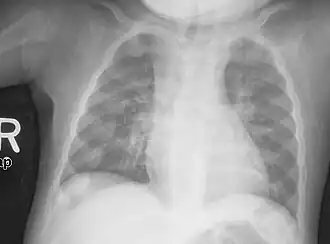

| Rachitic rosary on chest radiograph |

The rachitic rosary or beading of the ribs are the prominent knobs of bone at the costochondral joints of rickets patients. The knobs create the appearance of large beads under the skin of the rib cage, hence the name by analogy with the beads of a Catholic Christian rosary.[1]

Rachitic rosary may be felt during palpitation on a physical exam, or can be seen on a chest X-ray.[8] In severe cases including malnutrition, the bony protrusions may be seen through the skin.[9]